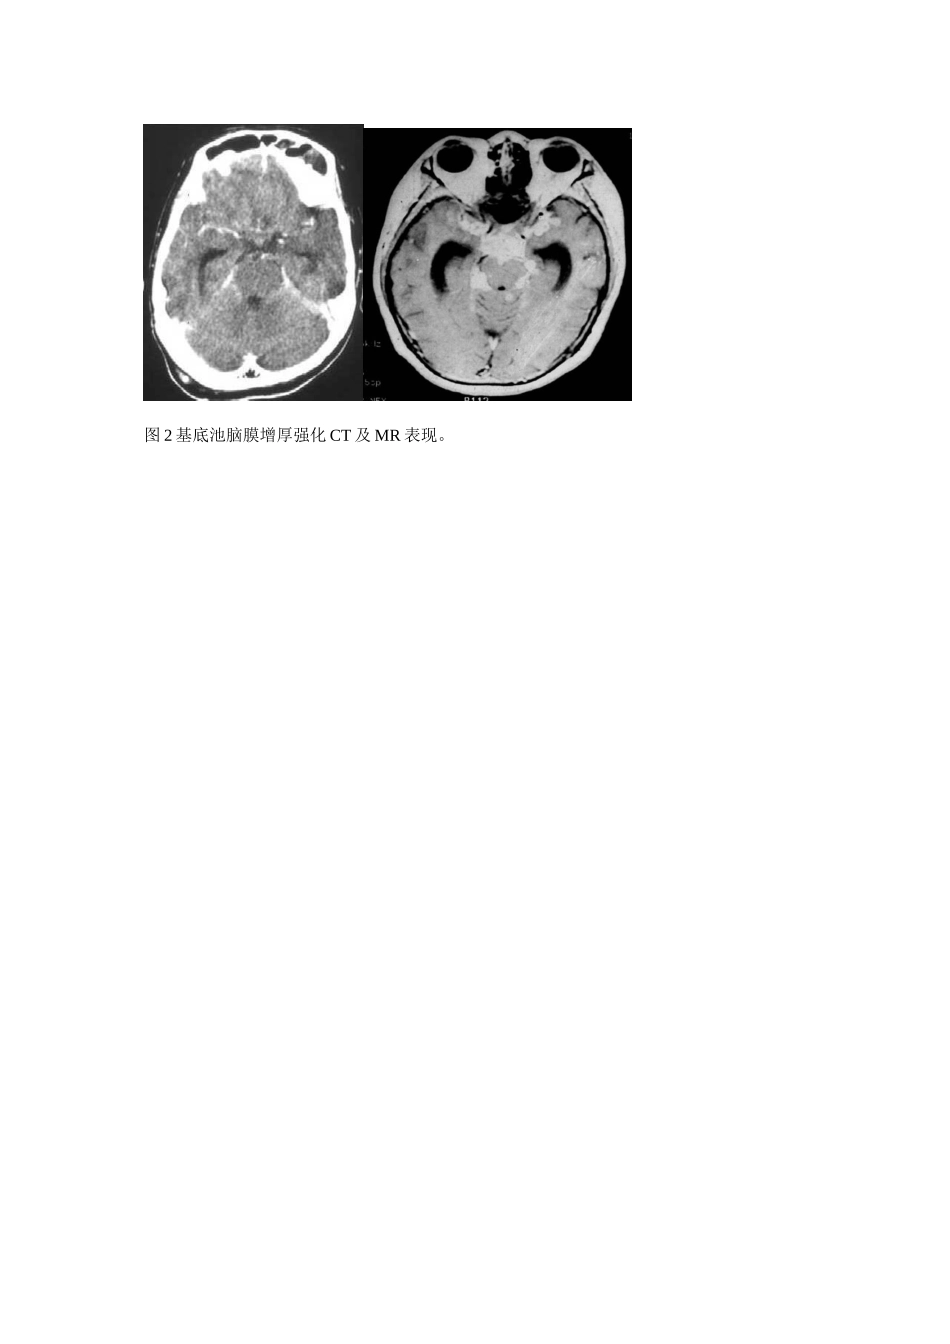

颅内结核CT及MR诊断(附八例报告)郑鹏*杨运红陈凤云戈必喜宜都市中医院443300【摘要】目的:通过对脑及脑膜结核CT及MR影像表现的深刻认识,提高脑及脑膜结核诊断正确率。方法,回顾性分析经临床证实的八例颅内结核CT或MR影像表现,比较影像初诊意见及临床最终诊断结论符合情况,分析其形成原因。并结合相关文献,结果:脑结核影像表现复杂,与多种颅内疾病有相似的影像表现。结论:结脑CT及MR影像表现复杂,与多种颅内疾病有相似的影像表现,必须结合临床及脑积液检查才能作出定性诊断。深刻认识其影像表现,有助于提高脑结核临床诊断正确率,【关键词】颅内结核体层摄影术X线计算机磁共振成像。颅内结核近年发病率有近上升趋势,早期诊断,可明显降低致死致残率,颅内结核一般分两种情况:1结核性脑膜炎及脑膜炎后遗症,2脑结核瘤。由于MR具有高密度分辨率,及对钆剂高度敏感性,头部MRI平扫及增强较CT平扫及增强有明显优势,具有更高病灶检出率。材料和方法本组8例均为临床诊断证实病例,年龄18-37岁,平均25岁,检查方法CT平扫及增强CT直接增强,MR平扫,MR平扫及增强。图1CT平扫基底池闭塞,高密度影充填,左侧丘脑梗塞,幕上积水。图2基底池脑膜增厚强化CT及MR表现。图3结核引起脉管炎图4结核瘤CT及MR增强呈环状,结节状强化。图5T2及TFLAIR系列部分病灶中心呈稍低信号图6病灶不规则多环状强化常见于结核,血吸虫,脑脓肿。图7结核瘤钙化结果:颅内结核影像表现复杂,与多种颅内疾病有相似的影像表现,必须结合临床及脑积液检查才能作出定性诊断。加深对颅内结核CT及MI影像表现的认识,缩小鉴别诊断范围,提示性诊断,有助于提高临床诊断正确率。讨论颅内结核影像表现一般分三种情况:1脑膜炎的表现,2脑结核瘤表现,3继发性表现:如交通性或梗阻性脑积水,脑外积液、脑梗塞、软化、出血及脑萎缩等,1脑膜炎的表现:结核性脑膜炎以脑底部病变为主,有脑底脑膜炎之称,CT平扫表现脑基底池密度增高,增强后可出现基底池强化,基底池闭塞,MRI表现T1WI脑基底池闭塞,信号增高,T2WI呈高信号,FLAIR系列呈高性号,增强脑基底池脑膜增厚强化。影像表现主要以化脓性脑膜炎、新型隐球菌脑膜炎鉴别,鉴别点主要是结核性脑膜炎以脑底部病变为主.单纯CT平扫还要和蛛网膜下腔出血鉴别.2脑结核瘤的表现,CT平扫表现为等或稍高密度结节,伴或不伴轻度水肿带,晚期病灶钙化呈高密度灶,MR上病灶中心短T2信号代表干酪样坏死,有一定特征性,CT及MR增强表现环型强化和小结节状强化。一般需和转移瘤,寄生虫感染,胶质瘤,脑脓肿鉴别。散在多发小钙化还要和脑囊虫,结节性硬化,TORCH等病鉴别。3继发性表现,CT及MRI诊断较容易,CT、MR血管成像有助于膜管炎的检出。以上表现常合并存在,以渗出性病变合并脑积水,结核球或脑积水并脑梗塞、脑萎缩居多,其种以中脑导水管梗阻引起幕上脑室扩张积水最多见,多种表现合并存在,在结脑鉴别诊断中具有一定特异性。参考文献:1,李果珍临床CT诊断学.北京:中国科学技术出版社,1994.128-1292,胡春洪汪文胜MRI诊断袖珍手册北京:人民军医出版社2007.783刘波临床MRI掌中宝广州:广东科技出版社2006.61*华中科技大学附属同济医院进修生